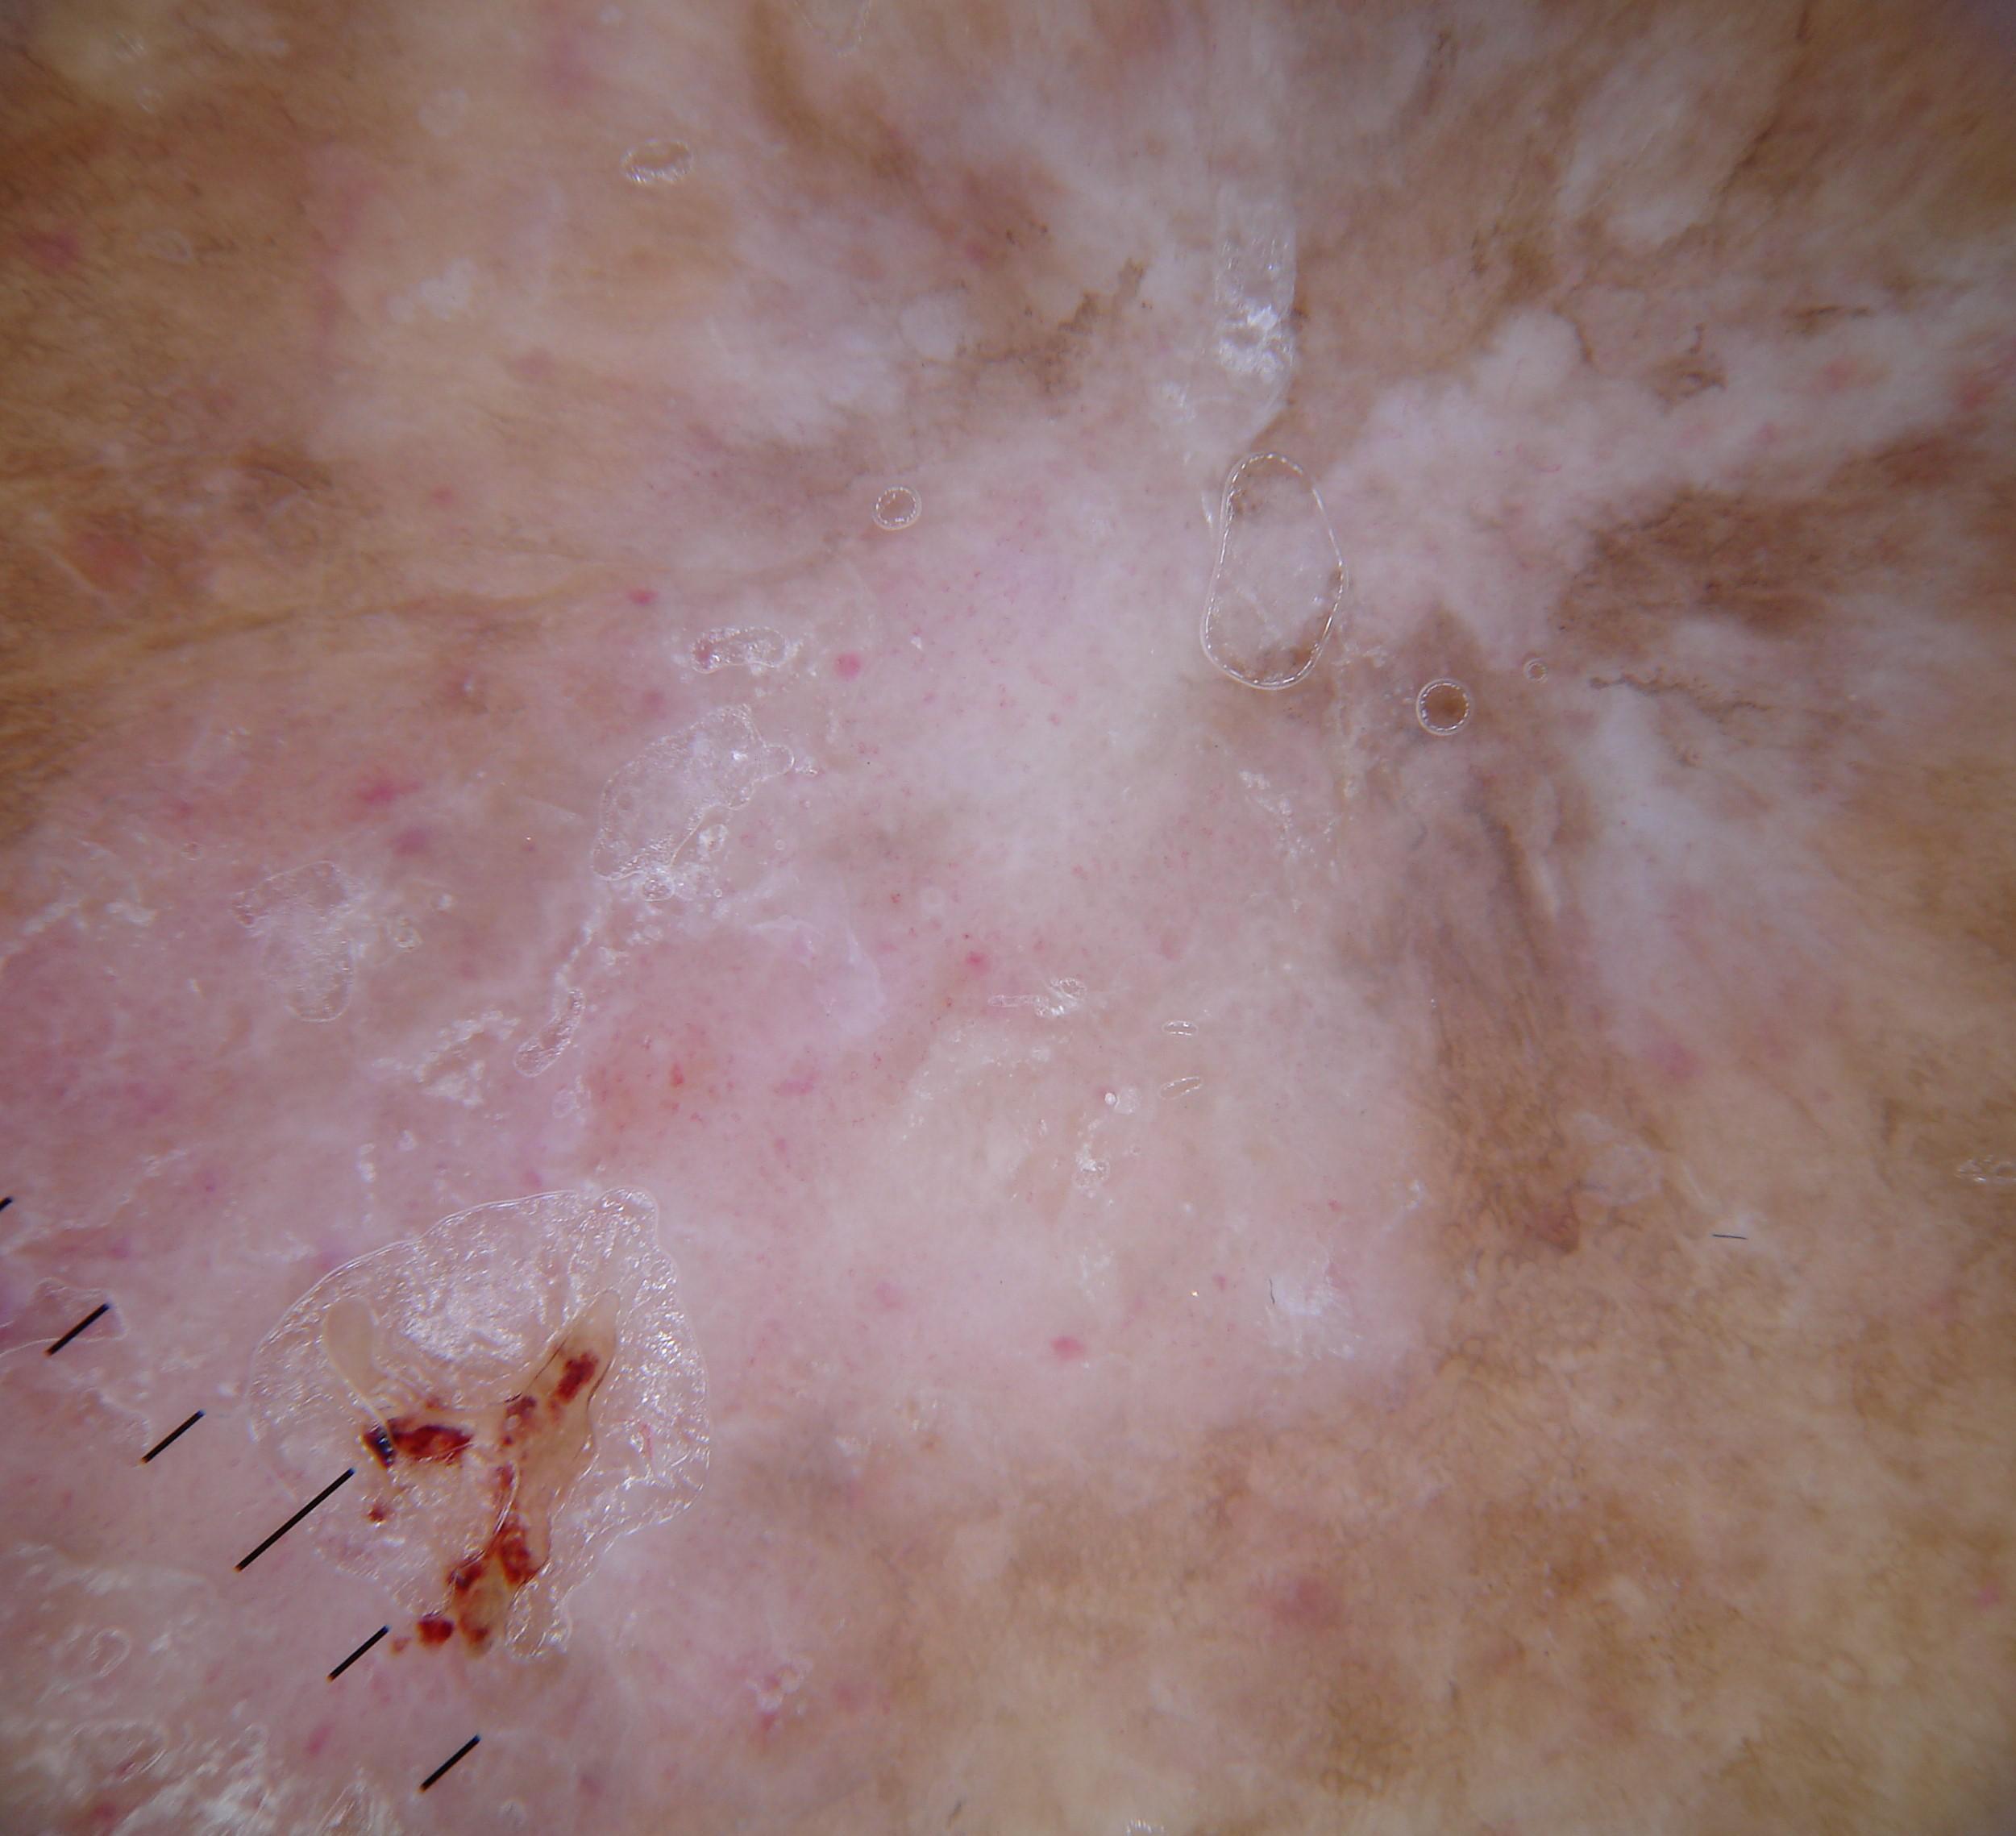

{

"age_approx": 75,

"anatom_site_general": "anterior torso",

"concomitant_biopsy": true,

"dermoscopic_type": "contact non-polarized",

"diagnosis_1": "Malignant",

"diagnosis_2": "Malignant melanocytic proliferations (Melanoma)",

"diagnosis_3": "Melanoma in situ",

"diagnosis_confirm_type": "histopathology",

"family_hx_mm": true,

"image_type": "dermoscopic",

"mel_thick_mm": "0.00",

"melanocytic": true,

"patient_id": "IP_1893317",

"personal_hx_mm": true,

"sex": "male"

}

"dermoscopic_type": "contact polarized",